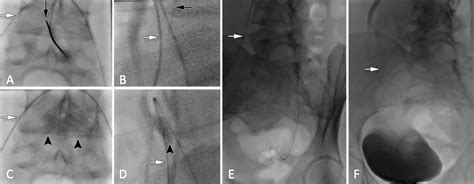

The procedure is typically performed under fluoroscopic or CT guidance to ensure accurate placement of the needle. The patient is usually positioned prone, and the needle is inserted through the skin and advanced to the target area. Once the needle is in place, the anesthetic and/or corticosteroid is injected.

• Fluoroscopy: Fluoroscopy is often used during interventional procedures to guide the placement of needles or catheters into the Superior Hypogastric Plexus.

Interventional procedures, such as nerve blocks or neurolysis, can provide targeted relief from chronic pelvic pain. These procedures are often performed under imaging guidance to ensure accurate placement of the needle or catheter.